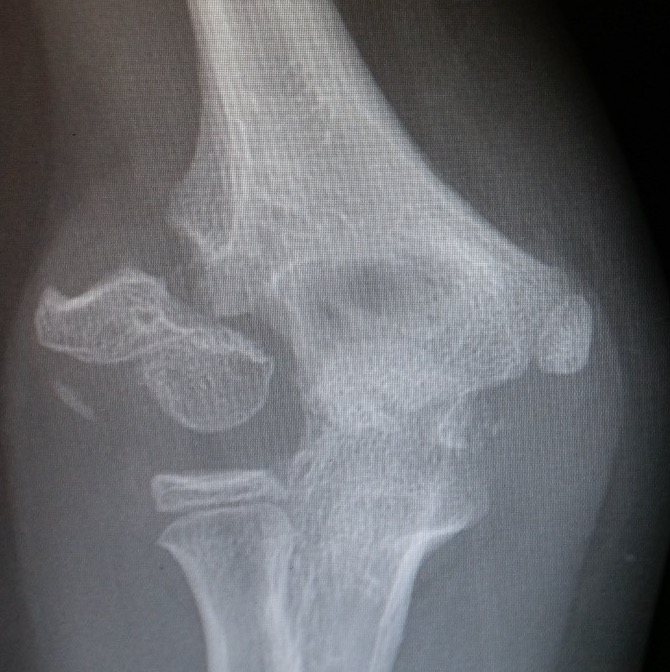

X-ray

Undisplaced

- typically metaphyseal flake

- looks minimally displaced on AP and lateral

- perform an internal oblique x-ray to exclude displacement

Displaced